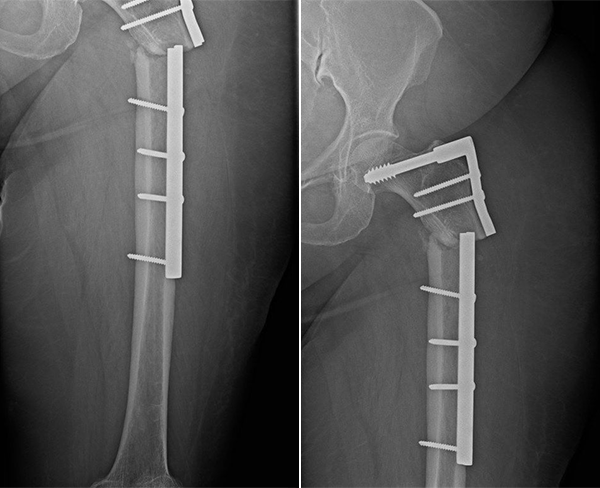

Având în vedere complexitatea cazului, s-a decis efectuarea unei intervenții chirurgicale de revizie, în mai multe etape. Aceasta a inclus îndepărtarea implantului anterior, curățarea focarului de fractură de țesutul fibros, realinierea fragmentelor osoase și stabilizarea femurului prin montarea unei tije centromedulare, completată de aplicarea unui substituent osos sub formă de pastă pentru umplerea defectului osos.

Intervenția chirurgicală a avut o durată de aproximativ 3 ore și a fost încadrată ca procedură de complexitate ridicată. Pacienta a fost spitalizată timp de aproximativ 5 zile, iar recuperarea articulară a fost inițiată precoce, imediat după intervenție. Pentru a preveni suprasolicitarea implantului, sprijinul complet pe membrul inferior stâng a fost amânat până la evaluarea radiologică de la 6 săptămâni postoperator.

Controalele imagistice efectuate la 6 săptămâni, 3 luni (vezi imaginea aici) și 6 luni au evidențiat o evoluție locală favorabilă, cu reluarea treptată a sprijinului și îmbunătățirea funcției membrului inferior stâng.

Utilizarea tijei centromedulare reprezintă standardul modern de tratament în multe tipuri de fracturi ale femurului, datorită avantajelor sale biomecanice și funcționale semnificative. Fiind poziționată în axul central al osului, tija preia mult mai eficient forțele de încărcare comparativ cu placa DCS, reducând stresul mecanic exercitat asupra implantului și favorizând o distribuție uniformă a presiunii.